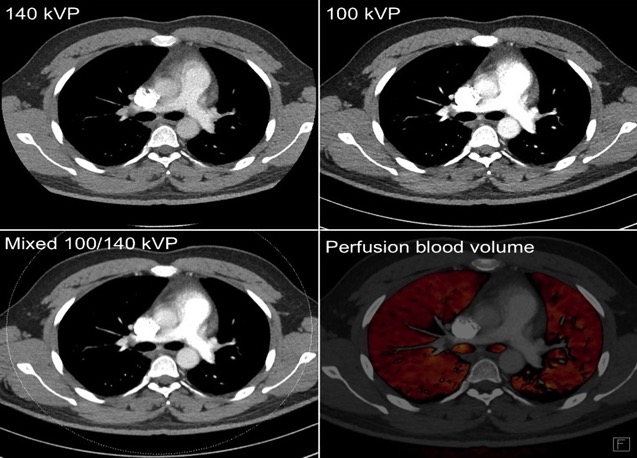

Dual energy perfusion maps can be used for quantitative assessment of the effects of PTE. They may also be used for follow up, post anticoagulation treatment.